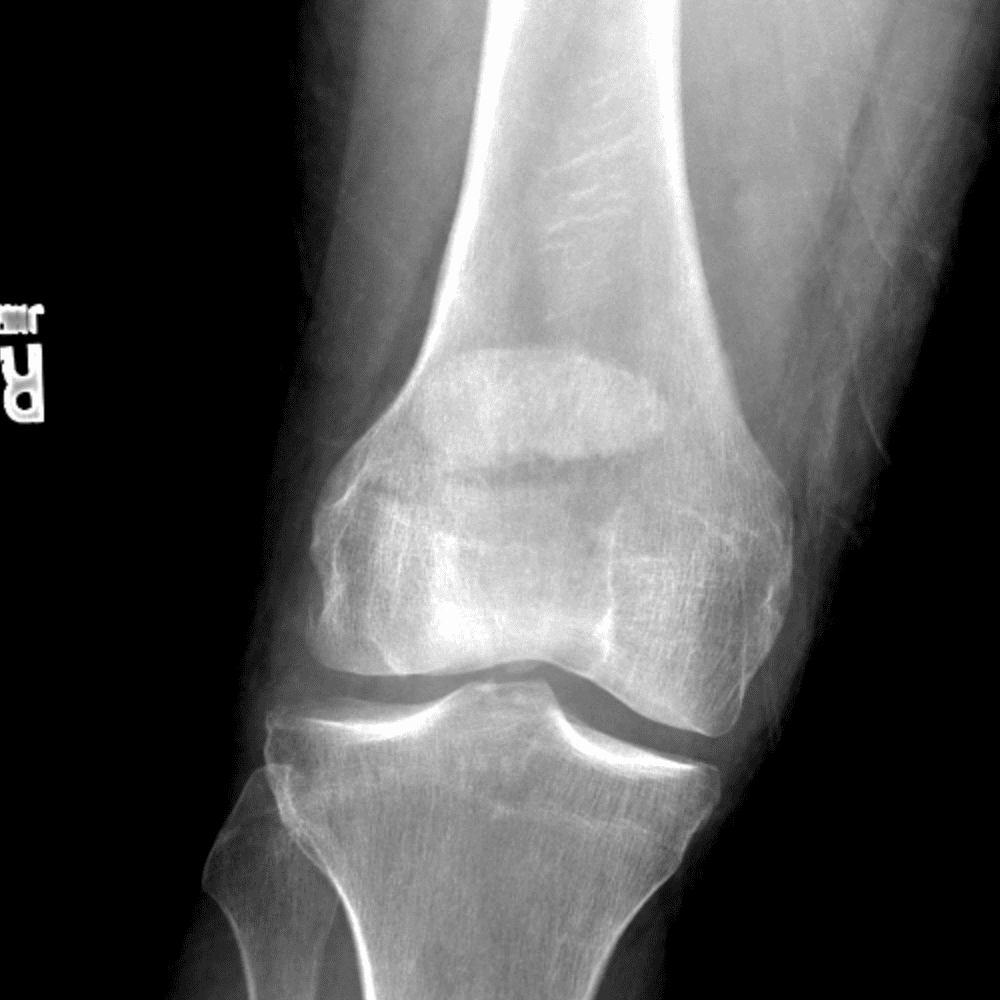

Simula o plantão incluindo casos sutis ou difíceis e alguns normais.